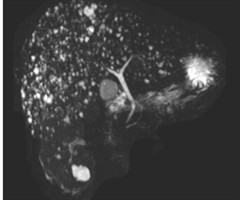

你见过肝脏里的 “繁星” 吗?一起了解胆管错构瘤

图1肝脏核磁共振见弥漫分布小圆形信号,呈“满天星征”肝脏内发现数百个结节,核磁共振成像中宛如满天繁星,这究竟是什么疾病?是否可治?这一疾病医学上称为“胆管错构瘤”,是一种较为罕见的肝脏良性病变。该病变主要发生在胆管系统,因正常组织发生异常组...